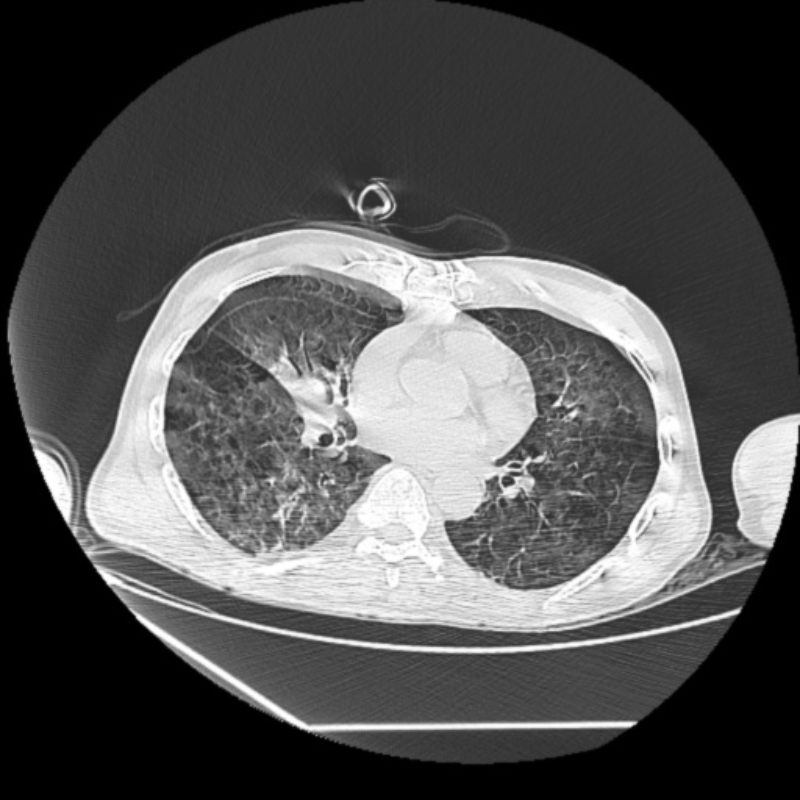

容伯伯到達急診醫(yī)學科急診搶救室后,還是神志昏迷、呼吸急促,心電監(jiān)測提示血氧飽和度低。急診搶救室吳文龍副主任醫(yī)師立即予以氣管插管接呼吸機輔助通氣治療,迅速完善血氣分析、CT等相關(guān)檢查后,擬“溺水”收入重癥醫(yī)學科。

文章配圖